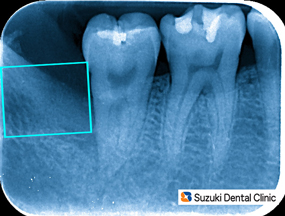

横向きに埋まってますので、引っ張って歯を抜くことは出来ません。難しい抜歯になりそうです。事前に抜歯方法と抜歯後に出やすい症状について説明します。

難しい抜歯 横向きに深く生えている歯を抜歯すると、①〜⑤のような症状が現れます。

①ツバを飲むと痛い

②大きく口が開けれない

③薬がきれると痛む

④冷たい物にしみやすくなる

⑤アゴがだるい

※これらの症状は2週間もすれば落ち着きますので、ご安心下さい。

抜歯後の痛み 抜歯は短時間で無事に終わりましたが、約2週間ほど術後の疼痛が出ました。このような場合、消毒、洗浄、投薬、塗り薬などを症状に合わせて対処しております。抜歯後のケアーもご安心下さい。